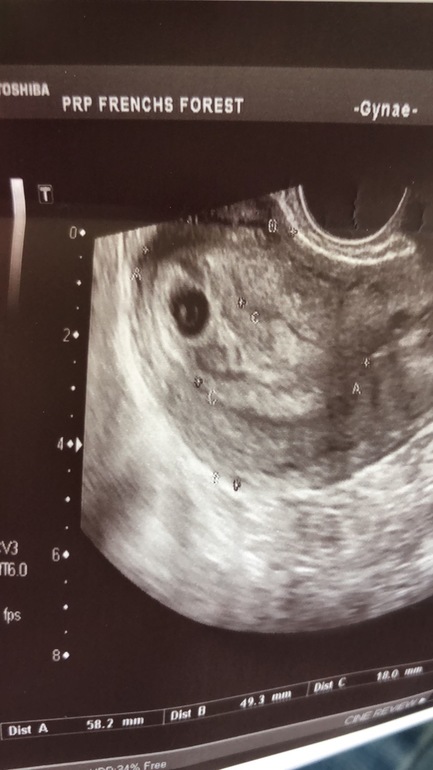

У меня вот такой результат УЗИ в 5 -6 нед. Только ЖМ. Эмбрион еще не видно. Сказали прийти через неделю на контроль.

А это результат УЗИ с сыном нед. в 7 по-моему. Прям чётко видно ЖМ и эмбрион в углу)))

Да,написала что эмбрион 2 мм. И желточный 3 мм. Но я эмбриона здесь не вижу

На узи я видела,то же что и на фото здесь)) именно это что более белое,она посчитала за эмбрион.